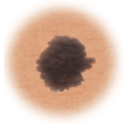

Color

When the color of the mole varies throughout

Color. The mole has different colors in it. It may be tan, brown, black, red, or other colors. Or it may have areas that seem to have lost color.